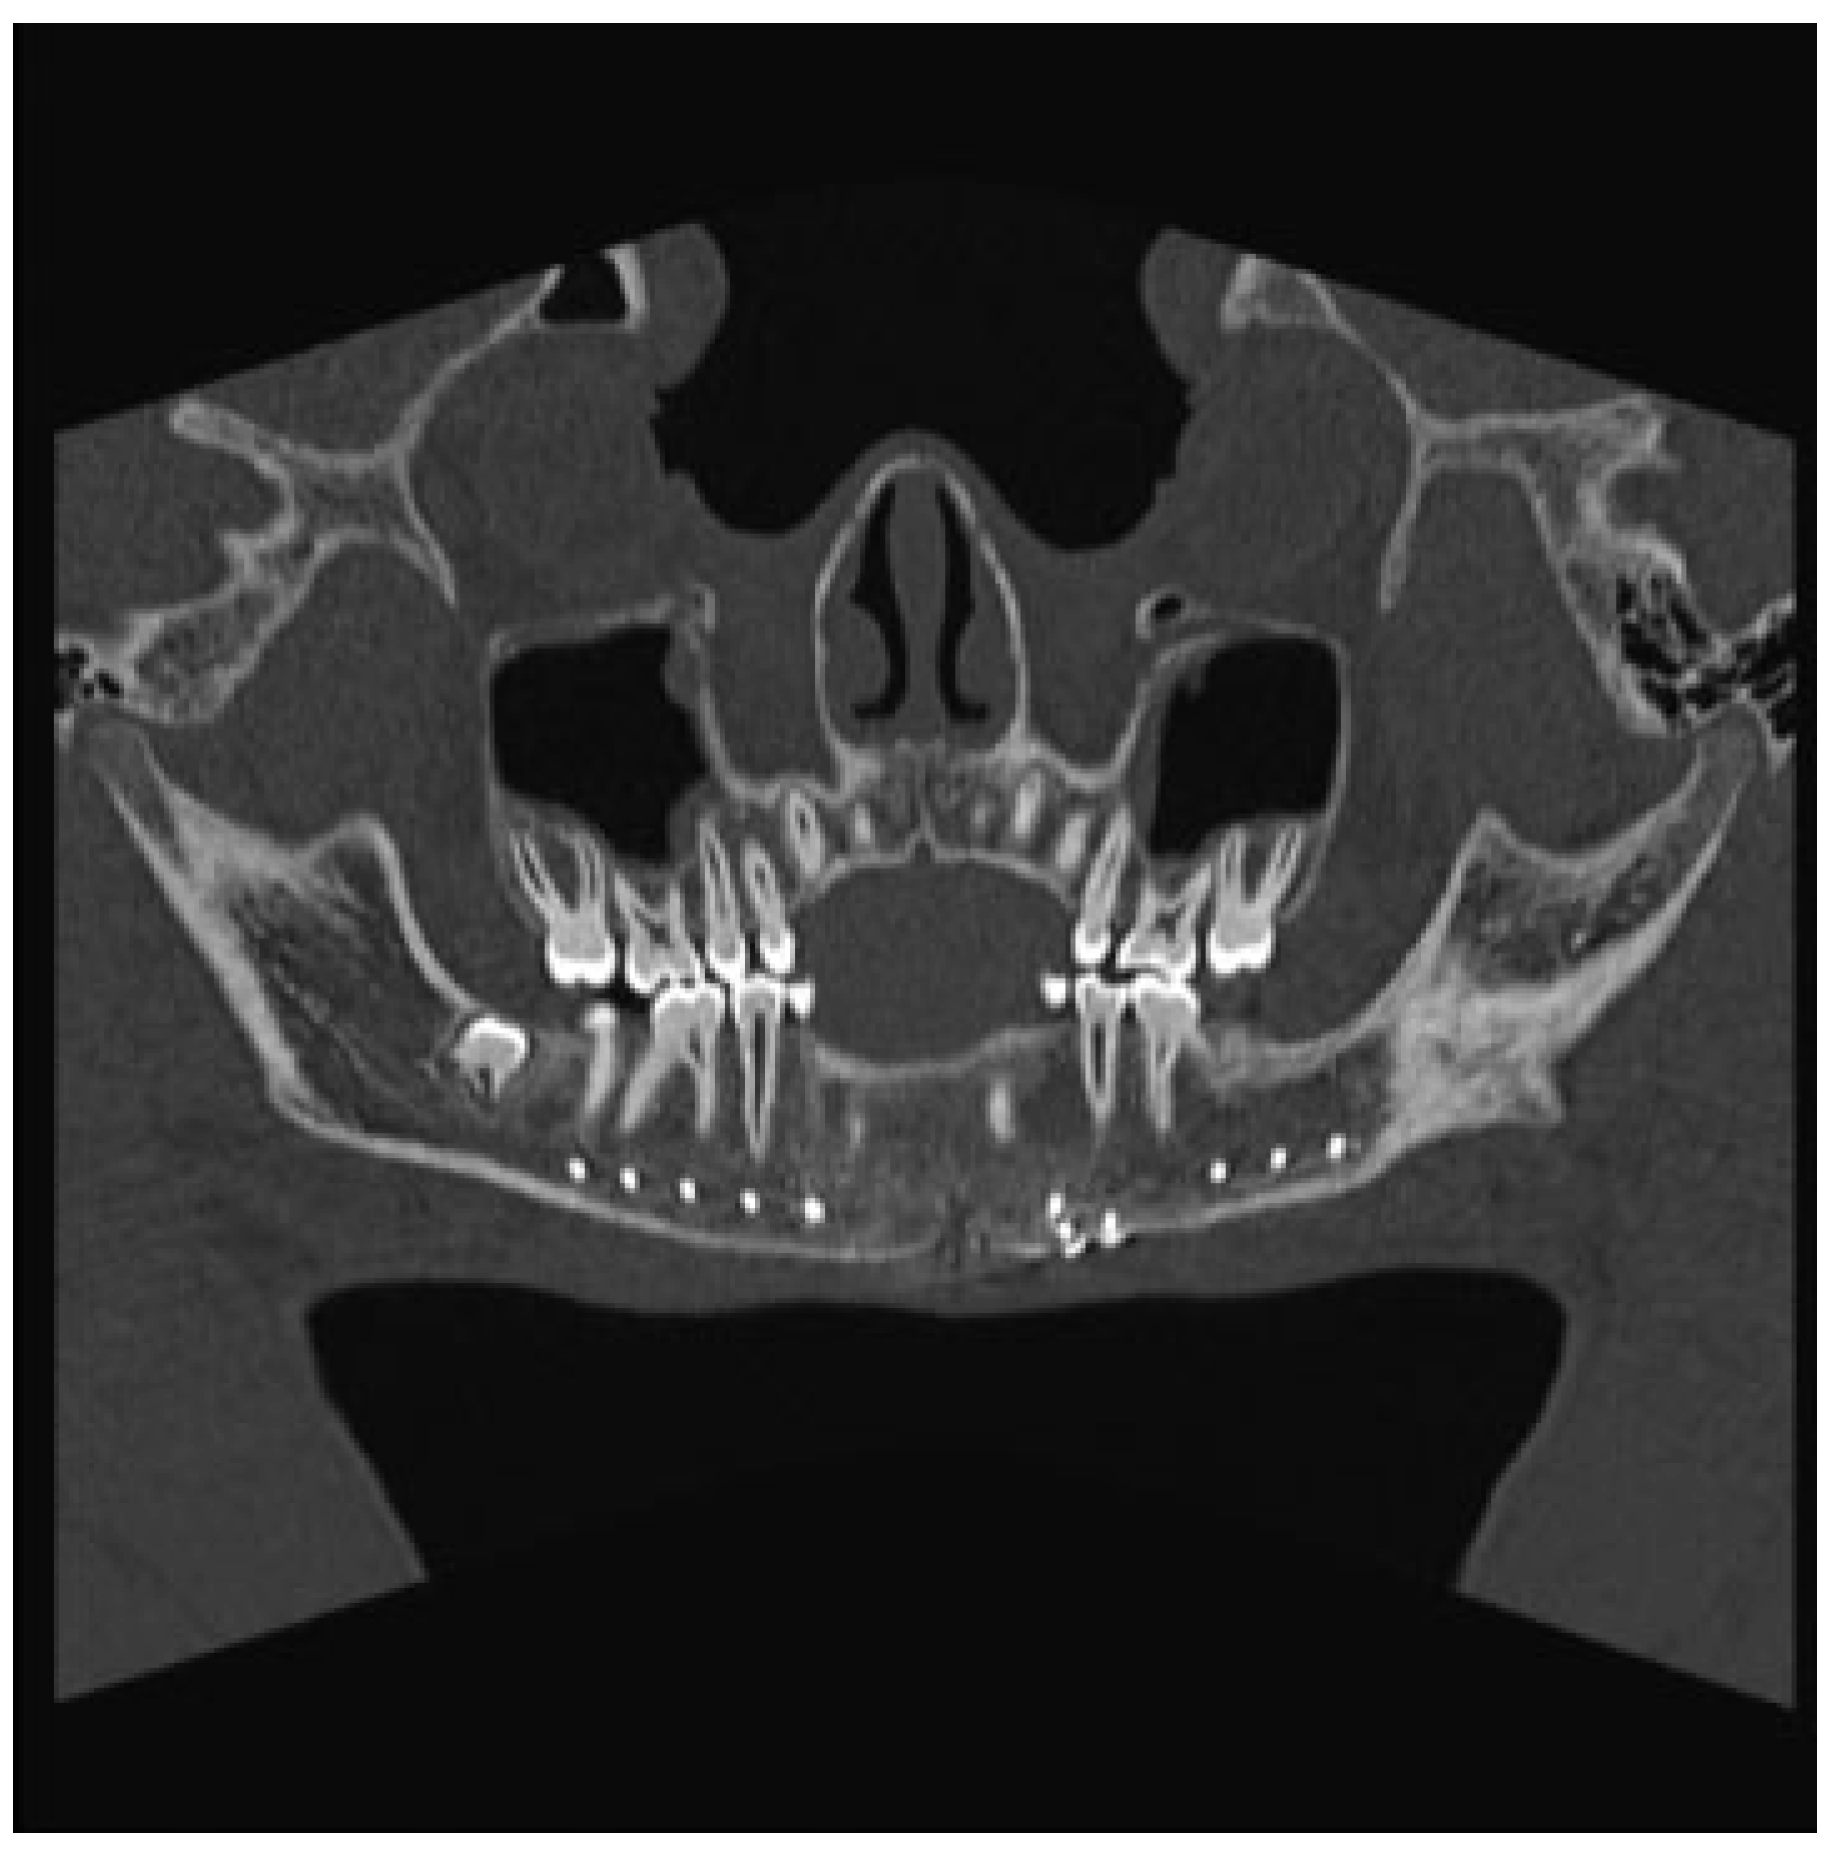

The Otolaryngology-Head and Neck Surgery department was consulted upon arrival to our ED. Physical examination revealed tenderness of the left side of the mandible and a visible intraoral step-off between the left mandibular lateral incisor and canine tooth. The CT was reviewed and demon- strated a significantly displaced fracture of the left para- symphysis. The fracture was deemed pathologic secondary to an apparent preexistent cystic lesion of the mandibular symphysis measuring 2.5 × 1.5 × 1.5 cm, with evidence of bony expansion (Figure 1).

Figure 1.

Coronal computed tomography (CT) scan revealing a parasymphyseal fracture in line with a cystic cavity.